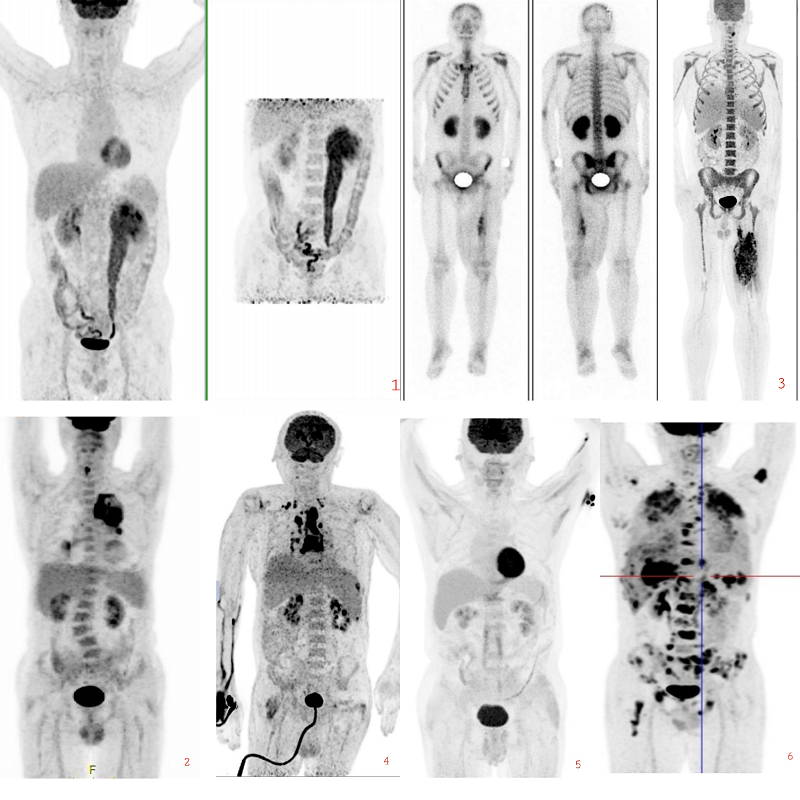

继续教育学组副组长富丽萍教授带领继教学组和青委会成员精心组织了6例疑难及罕见病例分析。北京协和医院罗亚平、北京大学第一医院张建华及北京大学人民医院李原主持了本次疑难病例讨论。来自各医院的的年轻医师精心准备、认真报告;现场各位医师积极参与讨论,分析内容丰富、条理清楚,使大家获益匪浅。最后,继续教育组长姚稚明对本次活动作了总结。

疑难病例MIP图像及讨论结果